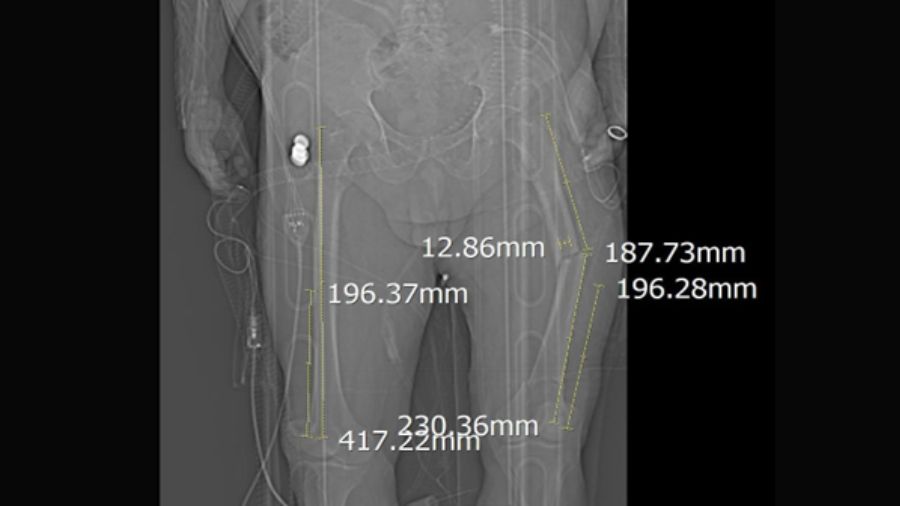

Preoperative planning